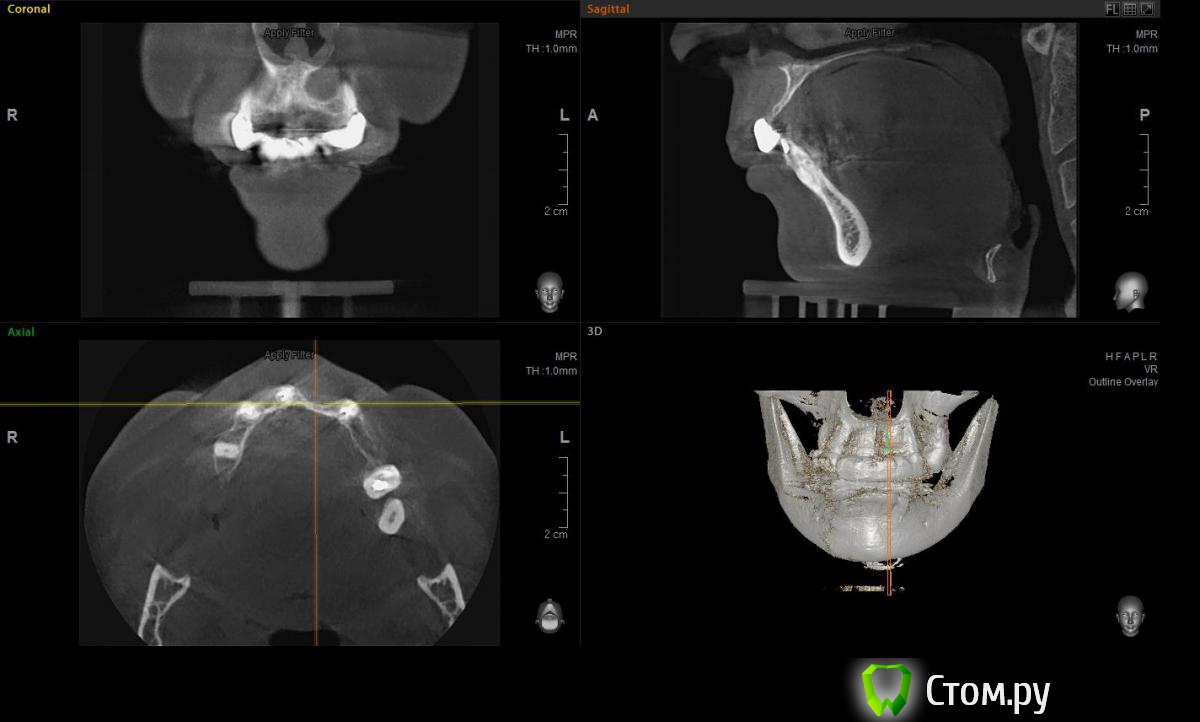

Евгений Ходыкин Опубликовано 22 июля, 2014 Автор Поделиться Опубликовано 22 июля, 2014 Дабы не плодить тем решил очередной случай выложить сюда Решили с пациенткой пока начать с в.ч. В планах имплантация в область отсутствующих 1.6, 1.4, 1.2, 2.1, 2.2, 2.4, 2.5. С 1.6 самому более менее все понятно, мануальных навыков хватит) Прошу помощи коллег относительно остальных областей. Фронт особливо печален... Забегая наперед скажу, что блоки еще не делал. Ауто точно пока брать не планирую, ибо нет даже теоретических навыков. Хочу начать все-таки с аллоблоков. У кого какие будут мнения, заранее спасибо) Ссылка на комментарий